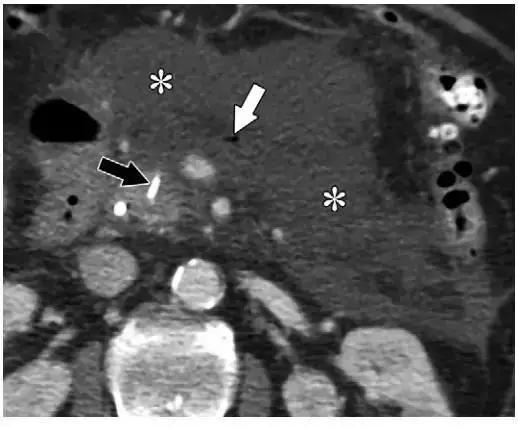

同时受累的亚型:表现为胰腺及胰周无强化坏死物,多累及小网膜囊和肾前间隙(图 3a)。

图 3 坏死性胰腺炎亚型在增强轴位 CT 的表现。a 胰腺和胰周同时受累的 58 岁女性患者,胰体无强化(*),正常强化的胰尾(黑箭头),小网膜囊内 ANC(白箭头)。b 仅胰周受累的 18 岁男性患者,可见一周为大片不均质密度(箭头),和 ANC 相符。胰腺实质密度正常(*)。c 仅胰腺实质受累的 33 岁男性患者,可见大片局限无强化的胰腺实质和脂肪密度(*),诊断为 WON。仅周边可见少量残余强化的胰腺实质(箭头)